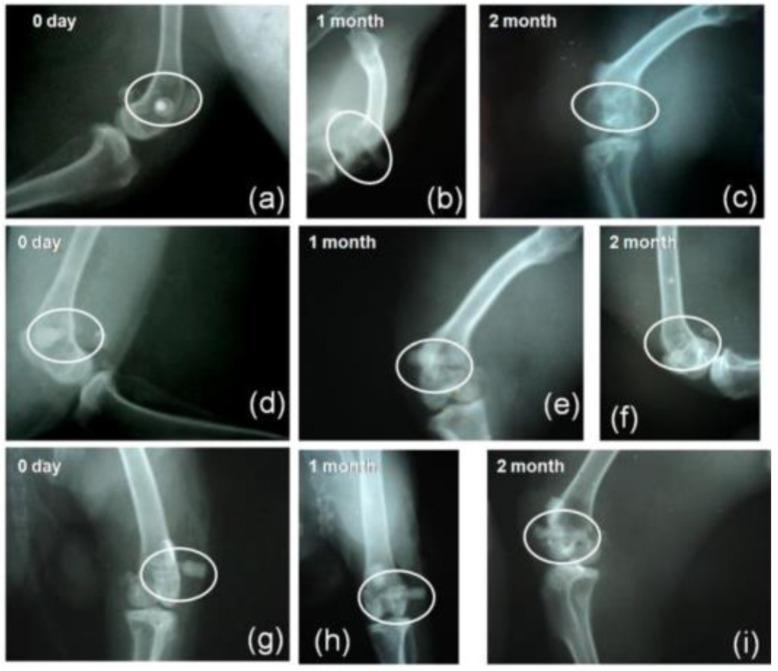

射线不透性有时是生物材料的一个基本特性,它有助于临床医生在介入前和介入后的放射成像过程中进行随访。由于其化学成分和结构,大多数生物陶瓷本质上是射线不透的,但仍可与射线不透剂掺杂/混合,以在医疗程序期间或之后增强其可视性。射线不透剂通常是元素周期表中的重元素,如铋(Bi)、锆(Zr)、锶(Sr)、钡(Ba)、钽(Ta)、锌(Zn)、钇(Y)等,或者是能增强射线不透性的相关化合物。射线不透的生物陶瓷也是生物聚合物和复合材料中有趣的添加剂,如今针对各种生物医学应用对其进行了广泛的研究和开发。本工作旨在概述射线不透的生物陶瓷,特别是为骨科、牙科和癌症治疗应用设计的结晶、非晶(玻璃态)和纳米结构生物陶瓷。此外,还将严格讨论由于添加射线不透剂而导致的母体陶瓷/生物聚合物的化学、物理和生物学性质的改变。我们还指出了这个令人兴奋的领域中生物陶瓷学家可以进一步探索的未来研究空白。